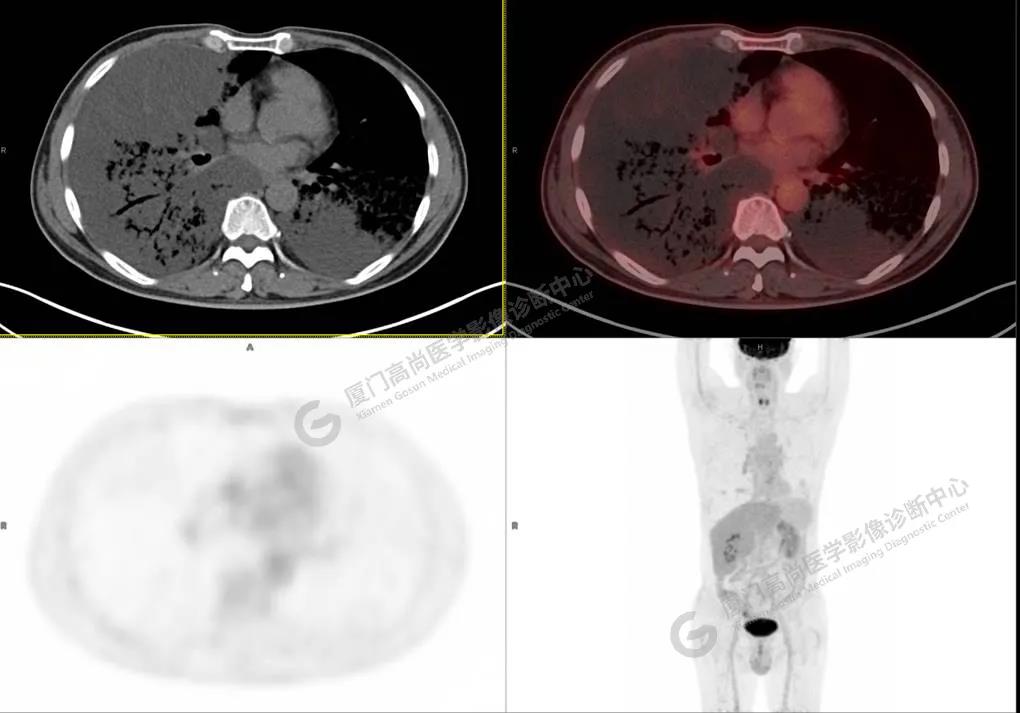

PET/CT影像圖

圖2

PET/CT所見:雙肺大片實(shí)變影及磨玻璃影,部分呈地圖樣改變,累及右肺尖,部分放射性攝取輕微增高,SUVmax 1.77,其內(nèi)見多發(fā)支氣管充氣征象。

影像診斷: 雙肺大片實(shí)變影及磨玻璃影,大部分代謝不高,局部代謝輕微增高,考慮肺泡蛋白沉積癥,建議病理學(xué)檢查或肺泡灌洗物檢查。